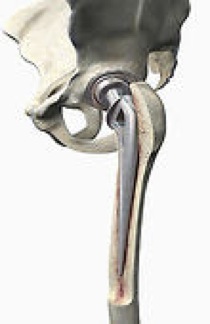

Loosening of the prosthesis from the bone

is the most important long-term problem. How long the bond will last depends on a number of factors.

Dislocation of the hip replacement

occurs in a small percentage of patients regardless of how good your surgeon is (some surgeons report as high as 4%). With the Anterior Approach or the Gluteal Split techniques of hip replacement, or the use of a large femoral head the risk of dislocation is greatly reduced, although it can still occur. Dislocation means that the metal ball slips out of the plastic socket. In the first six weeks after the surgery, the ball is only held in the socket by muscle tension. During this time, before scar tissue forms around the ball, and before muscle strength returns, the hip is more likely to dislocate.